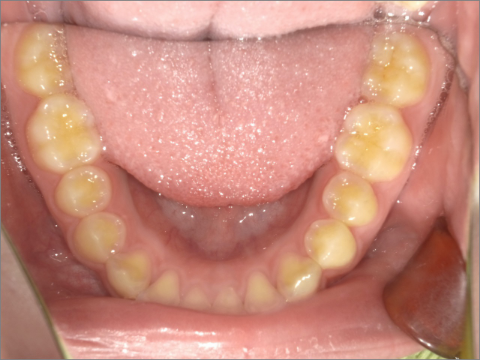

ご年齢 15歳女性 治療期間 2022/07/02〜2023/12/02(1年5ヶ月)

診断 110,000円(税込) アライナー 660,000円(税込) リテーナー 55,000円(税込)

ご年齢 15歳女性

治療期間 2022/07/02〜2023/12/02(1年5ヶ月)

診断 110,000円(税込)

アライナー 660,000円(税込)

リテーナー 55,000円(税込)

BEFORE

AFTER